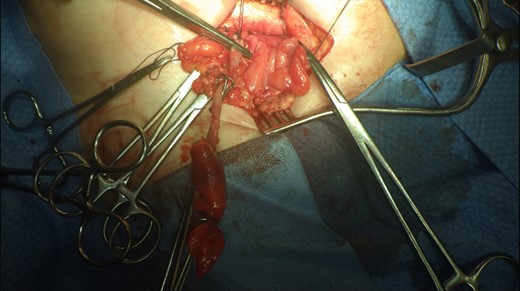

This 82-year-old lady presented with a sudden painful right sided groin swelling not previously noticed. She had no features of obstruction and was opening her bowels and not vomiting. Her medical background included left sided femoral hernia repair in 2005, coronary artery bypass graft and bilateral total knee replacements. On examination her abdomen was soft with the presence of a tender, irreducible swelling in the right groin, inferolateral to the pubic tubercle. She had good bowel sounds and there was stool present in the rectum on PR examination. A full set of blood tests demonstrated no abnormality. A CT abdomen and pelvis demonstrated an incarcerated right sided femoral hernia containing an 8 mm long inflamed appendix with a small amount of localized free fluid and inflammation indicative of De Garengeot’s hernia with underlying acute appendicitis (Fig. 1). The hernia sac diameter measured 2 mm on CT scan. She was taken to theatre for an open Lockwood repair of her femoral hernia and an appendicectomy. Following an initial Lockwood incision over the lump, dissection was performed down to the hernia sac also exposing the inguinal ligament (Fig. 2). The tightness of the femoral ring made mobilization of the appendix difficult. By partially incising the inguinal ligament superior to the femoral ring, the appendix was freed, and on inspection showed inflammation particularly towards the tip (Fig. 3). The caecum was then reduced and the inguinal ligament was repaired with non-absorbable suture. The femoral hernia was then repaired with a small funnel of ultrapro mesh. Appendicectomy was then performed in the usual fashion via the Lockwood incision leaving a slightly longer stump than usual (Fig. 4).

Vermiform appendix freed from hernial sac showing inflammation towards the tip.